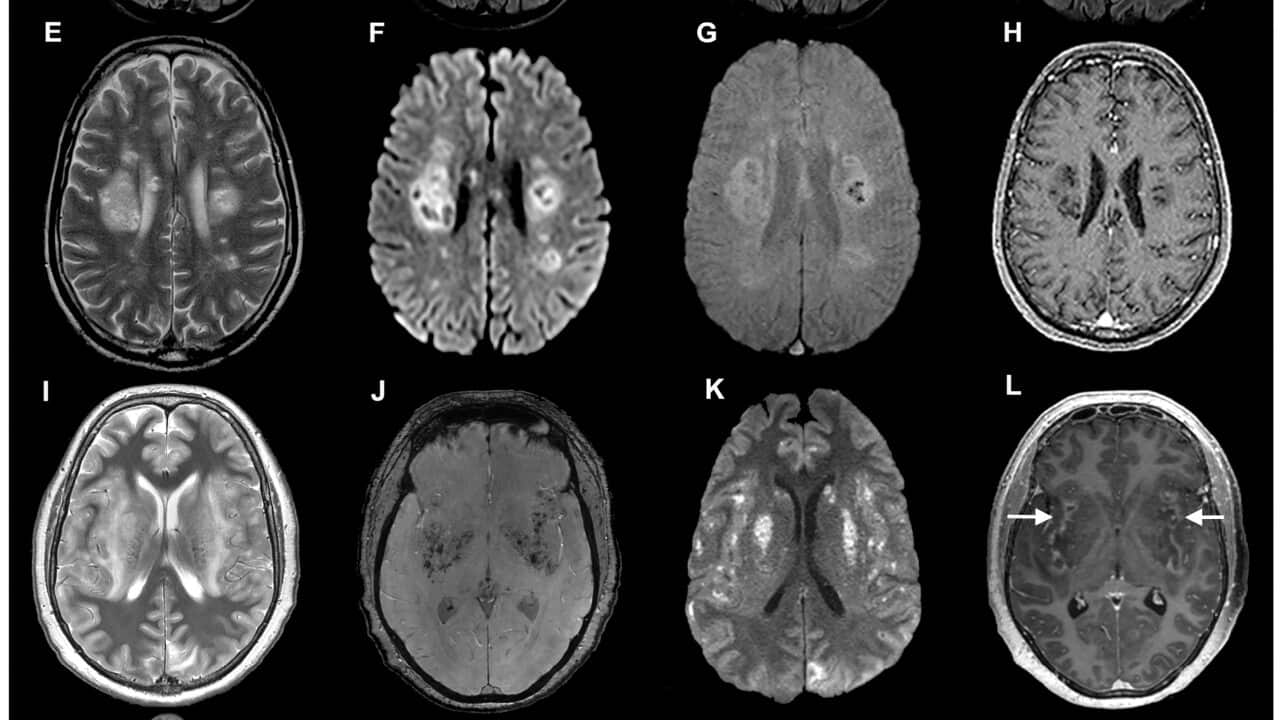

وكانت المرأة قد دخلت في أوقات متفرقة إلى المستشفى بسبب ألم في المعدة وسعال جاف وتعرق ليلي، وبعد أشهر عانت من الاكتئاب والنسيان مما أدى إلى إجراء فحص للدماغ.

ويعتقد الأطباء أن المرأة أصيبت بالدودة عندما كانت تفتش عن نوع من الاعشاب التقليدية المحلية بالقرب من منزلها. وتعد هذه أول حالة بشرية على الإطلاق لعدوى من هذا النوع حيث انتقلت العدوى من الحيوان الى البشر.